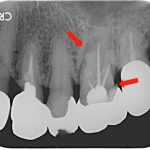

前歯の根元の黒いところが気になる 古い被せ物をセラミックに変えた症例

治療前 治療後 年齢・性別 40代女性 相談内容 前歯の黒いところが気になる カ ...